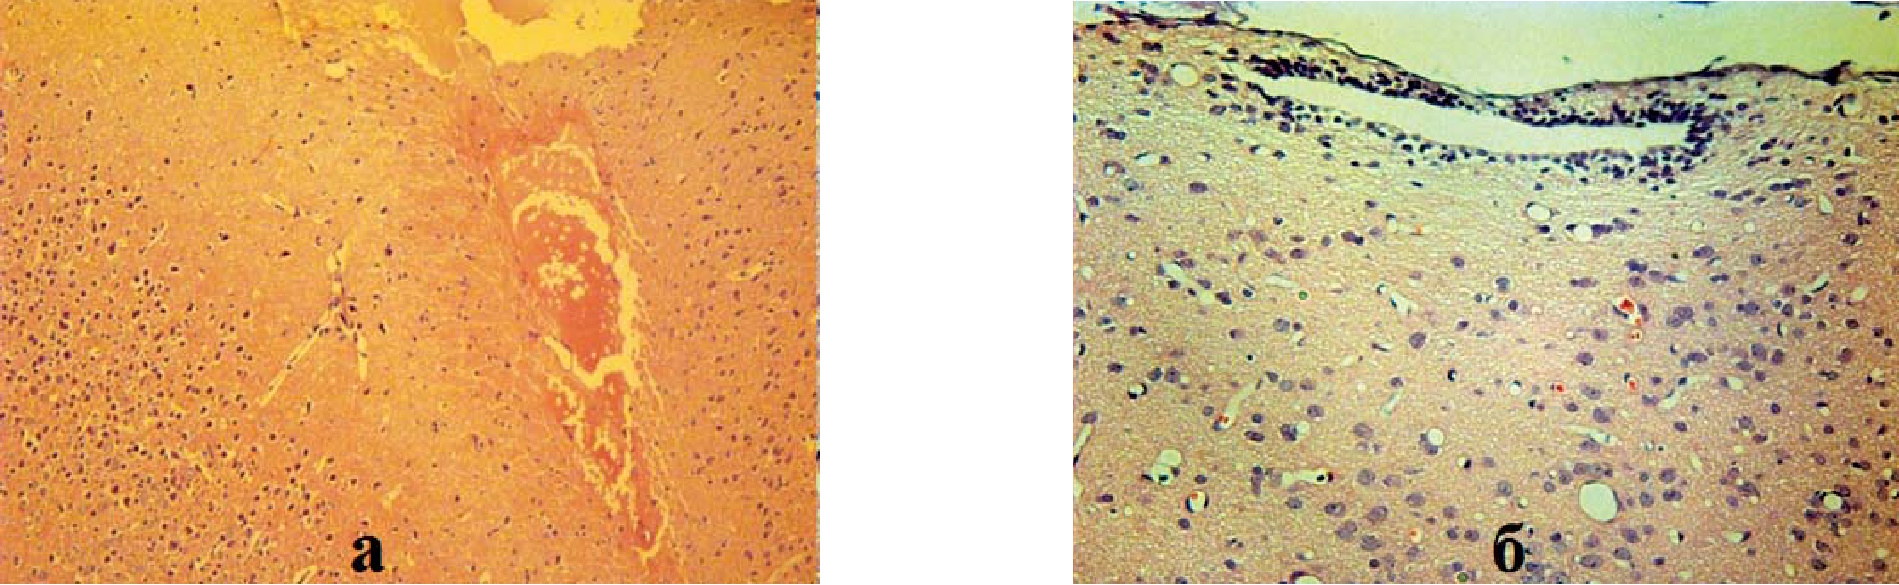

В выполненных ранее работах нами совместно с Санкт-Петербургским государственным педиатрическим медицинским университетом [2, 6, 7, 10] были получены и усовершенствованы экспериментальные модели целого ряда болезней человека, которые характеризуются высокой смертностью, резистентностью к существующей терапии и являются актуальными для клинической медицины – ишемический инсульт, застойная сердечная недостаточность, токсический цирроз печени, критическая ишемия нижних конечностей, синдром короткой кишки. На этих экспериментальных моделях была показана безопасность, эффективность клеточной терапии, оптимальные количества и пути доставки клеток к поврежденному органу или ткани. В частности, показано значимое улучшение неврологического статуса у крыс, перенесших ишемический инсульт, в ответ на клеточную терапию, выполненную на 14-е сутки, а не в первый или третий дни ишемической атаки, что нашло морфологическое обоснование (рис. 2) [4].

Рис. 2. Результат введения мононуклеаров красного костного мозга через 14 суток после инсульта: а – неполная репаративная регенерация инфаркта мозга с формированием кисты, ув. ×100; б – эпендимальная пролиферация в стенке III желудочка, ув. ×200. Окраска гематоксилином и эозином